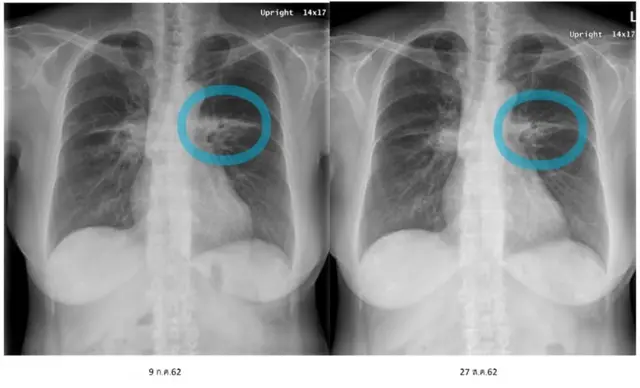

“แต่พอมาระยะสี่ ก็เป็นระยะที่ผ่าตัดไม่ได้แล้ว” หมอบัว ยอมรับ “อย่างคุณแม่ มี (มะเร็ง) ก้อนใหญ่อยู่ที่ปอดขวาก้อนหนึ่ง ปอดซ้ายก้อนหนึ่ง และมีจุดเล็ก ๆ กระจายอยู่ที่ชายปอด ไปผ่าทำอะไรไม่ได้”

ยามุ่งเป้านั้นมีหลายประเภท และแสดงผลกับผู้ป่วยแต่ละคนไม่เท่ากัน ในกรณีแม่ของหมอบัว ได้รักษาด้วยยามุ่งเป้าตัวแรก 13 เดือน แต่ก้อนมะเร็งกลับเริ่มใหญ่ขึ้น ทำให้ต้องเปลี่ยนเป็นยามุ่งเป้าตัวที่ 2 และใช้อยู่นาน 23 เดือน ถึง ต.ค. 2559 จนเมื่อเซลล์มะเร็งไม่ตอบสนองกับยามุ่งเป้าตัวนี้ จึงต้องตรวจชิ้นเนื้อที่ปอดอีกครั้ง เพื่อดูการเปลี่ยนแปลง และเมื่อพบว่ามีการกลายพันธุ์ในแบบที่ทานยามุ่งเป้าตัวที่ 3 ได้ จึงเป็นตัวเลือกรักษามาถึงปัจจุบัน

“จนปัจจุบัน โรคมะเร็งของคุณแม่นิ่งแล้ว ตอนนี้ก็เข้าสู่ปีที่ 10 ของการรักษาแล้วค่ะ” แต่ “ก้อน (มะเร็ง) จะหายไปสนิทไหม ไม่ล่ะค่ะ เมื่อเป็นระยะสี่ ก็ต้องยอมรับว่าโรคจะไม่หาย แต่สามารถควบคุมได้”